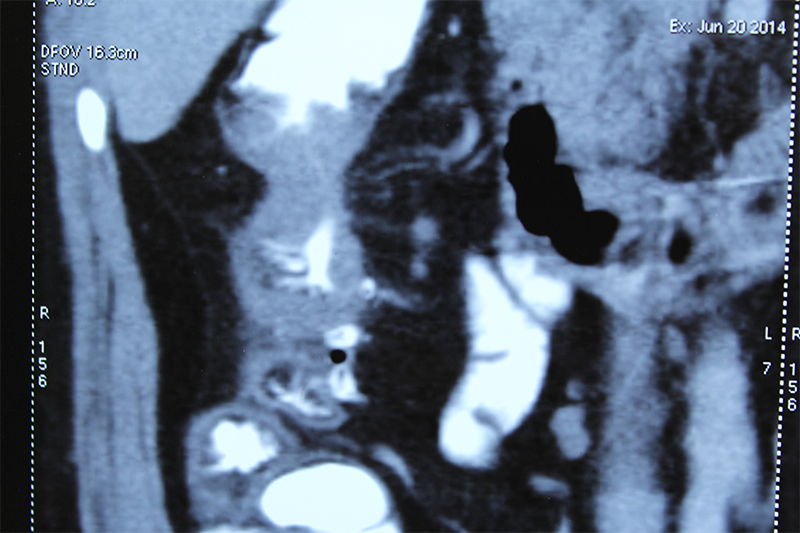

45 year old gentleman was diagnosed with right colon cancer (poorly differentiated adenocarcinoma) and solitary metastasis to liver. He underwent a one stage surgery (right hemicolectomy for colon cancer and resection of liver metastasis). The surgery was followed by multiple cycles of chemotherapy. A chemoport was placed for the same. The patient lived for 4 years after diagnosis of advanced poorly differentiated colon cancer.

Patients diagnosed or suspected to have a colon / rectal cancer are subjected to multiple tests. The most important ones are checking serum tumor marker CEA (carcinoembryonic antigen), colonoscopy and biopsy, CT scan of abdomen & pelvis and sometimes a PET CT study. The CEA is useful in diagnosing cancer and also to follow treatment response (surgery or chemotherapy). However all patients may not have a raised CEA. CT / PET-CT is done to see if tumor can be operated and removed or has it spread beyond the intestine in the surrounding area or distant organs like liver, lungs etcetera. A colonoscopy ( endoscopy of large intestine to visualize it from within) helps to take a biopsy and also checks whether cancer is in only one part or multiple parts of colon (synchronous primary tumor). The biopsy sample is run through many tests apart from regular histopathology. This includes immunohistochemistry (IHC), genetic tests for mutations (KRAS, BRAF, microsatellite instability) etcetera. These tests help in deciding prognosis, treatment plan treatment sequence, chemotherapeutic drugs to be used. In short have a major impact on treatment. However they are very expensive too.